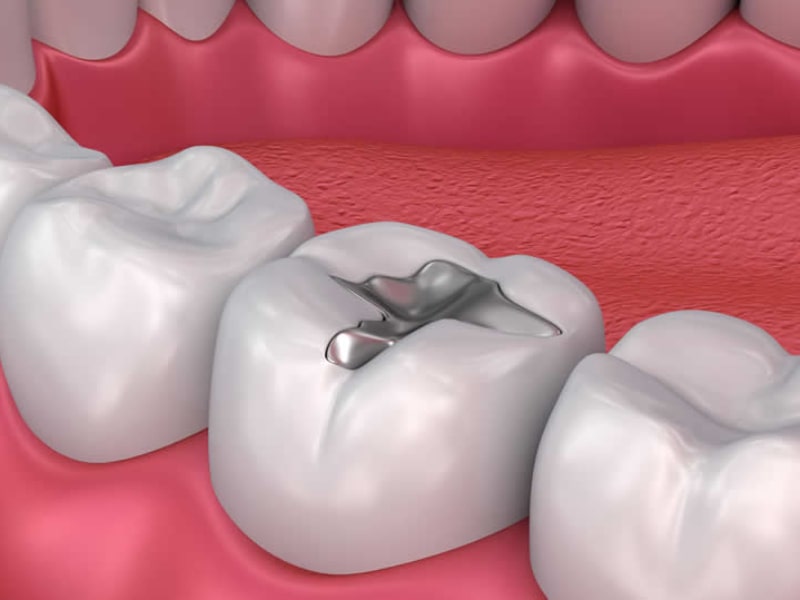

Dental filling, which contributes both in terms of health and aesthetics by preventing tooth loss in the mouth, is applied to decayed, broken or cracked teeth. How the tooth filling, which is one of the treatments used to protect oral and dental health, is made, may vary depending on why the tooth is damaged and where the tooth is located. After the filling process, tenderness and pain can be seen up to 12 hours. After the procedure, food should not be eaten for a certain period of time, hard, cold and hot foods should not be consumed.

Composite filling is a type of filling that is applied especially to the visible and front tooth parts of the tooth. There are two varieties. Depending on the situation, the patient’s tooth is treated with one of two conditions. Composite filling, which adapts to the tooth color, makes the tooth more durable. The application can be completed in several times, not in one go. It is a more expensive application compared to the amalgam filling type.